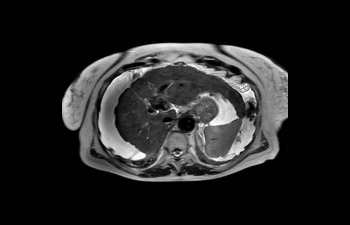

Ingenia Elition fornisce un'eccellente qualità delle immagini ed esegue esami RM a una velocità fino al 50% più elevata¹.

Velocità applicata sempre e correttamente.